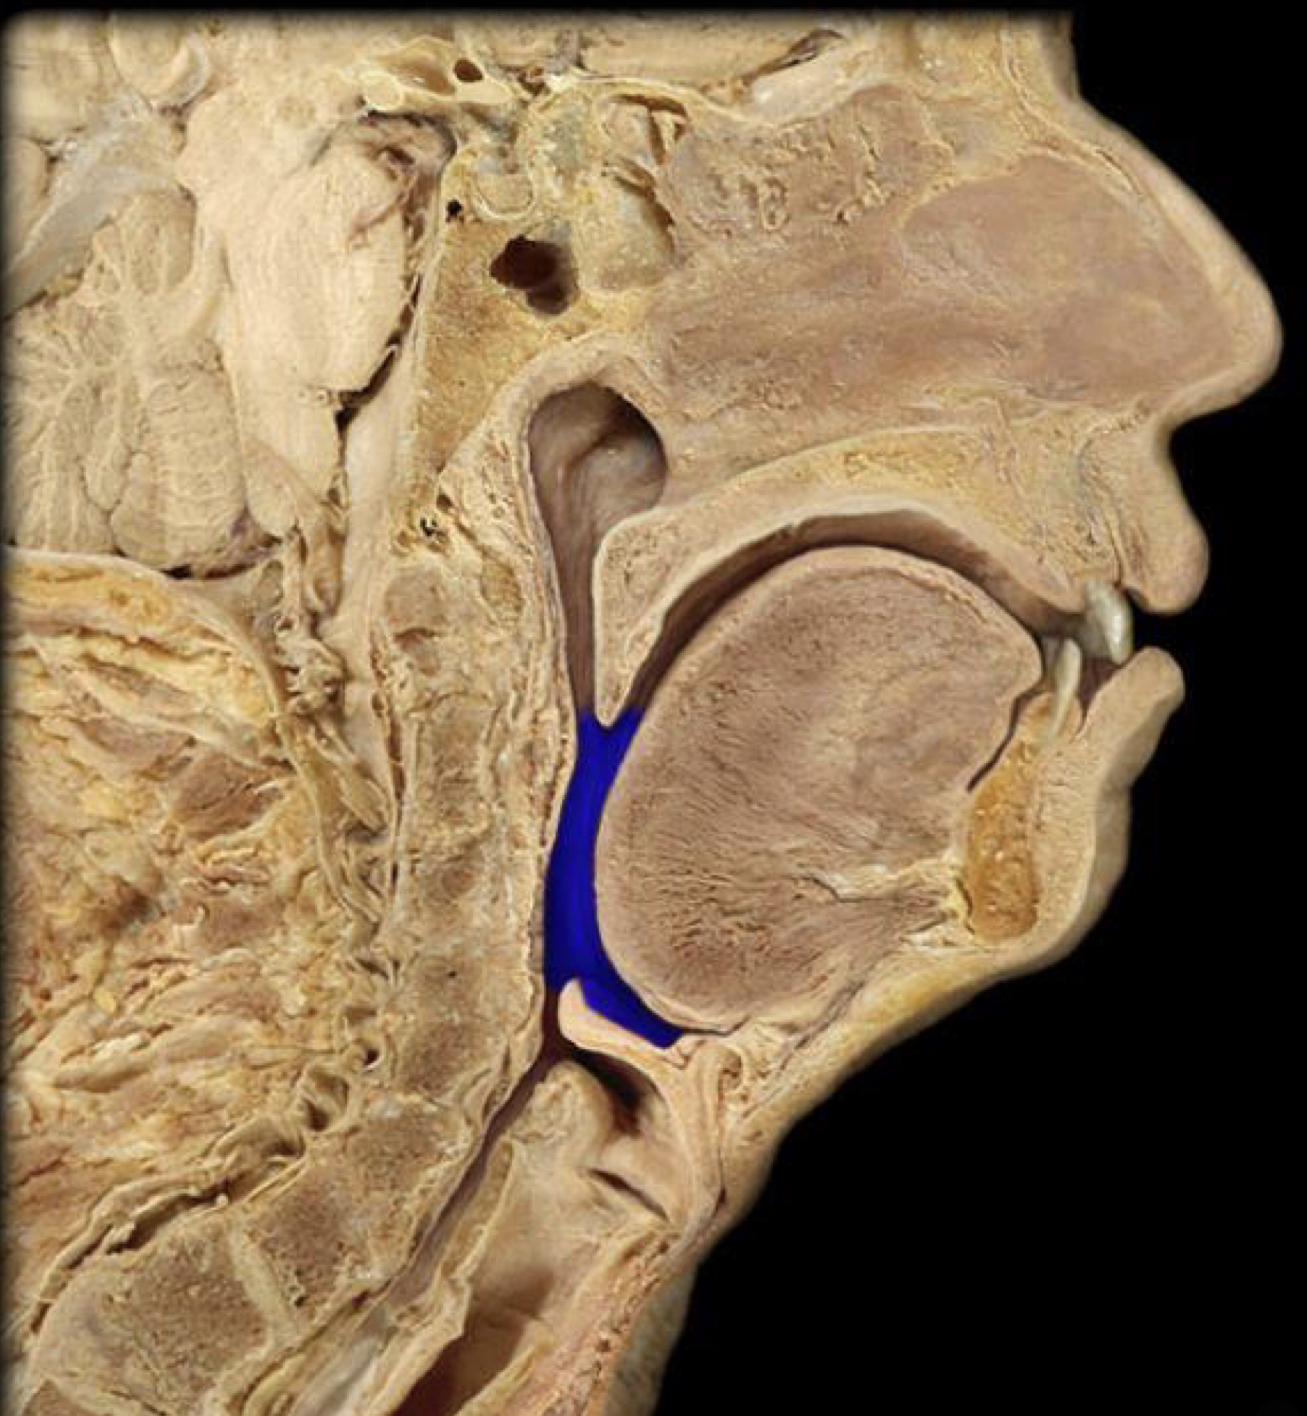

What structure is highlighted in blue?

External naris